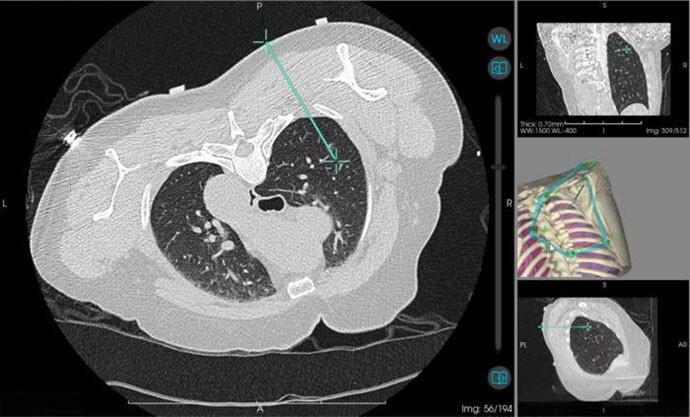

當天,該院心胸外科主任陽諾帶領消融團隊開展手術,他介紹,在術前,穿刺手術機器人系統基於患者電腦斷層掃描影像,能自動構建詳細的肺部3D立體模型,清晰呈現結節與周圍血管、氣管等重要組織的位置關係。

“它就像一位‘智能導航員’,精準規劃穿刺路徑、角度與深度,有效避開血管、氣管等重要組織結構,將誤差控制在毫米級”,陽諾說。

術中,機器人就像有了“智慧眼睛”和“穩定雙手”,整個過程機械臂平穩導航,無需調針,減少了電腦斷層掃描次數和患者的輻射暴露,機器人的應用避免了人為因素可能帶來的穿刺偏差,從而減少對周圍正常組織的損傷,降低了氣胸、出血等並發症的發生率,也縮短了手術時間。

↑圖說:圖為機器人引導下實際穿刺路徑(供圖)